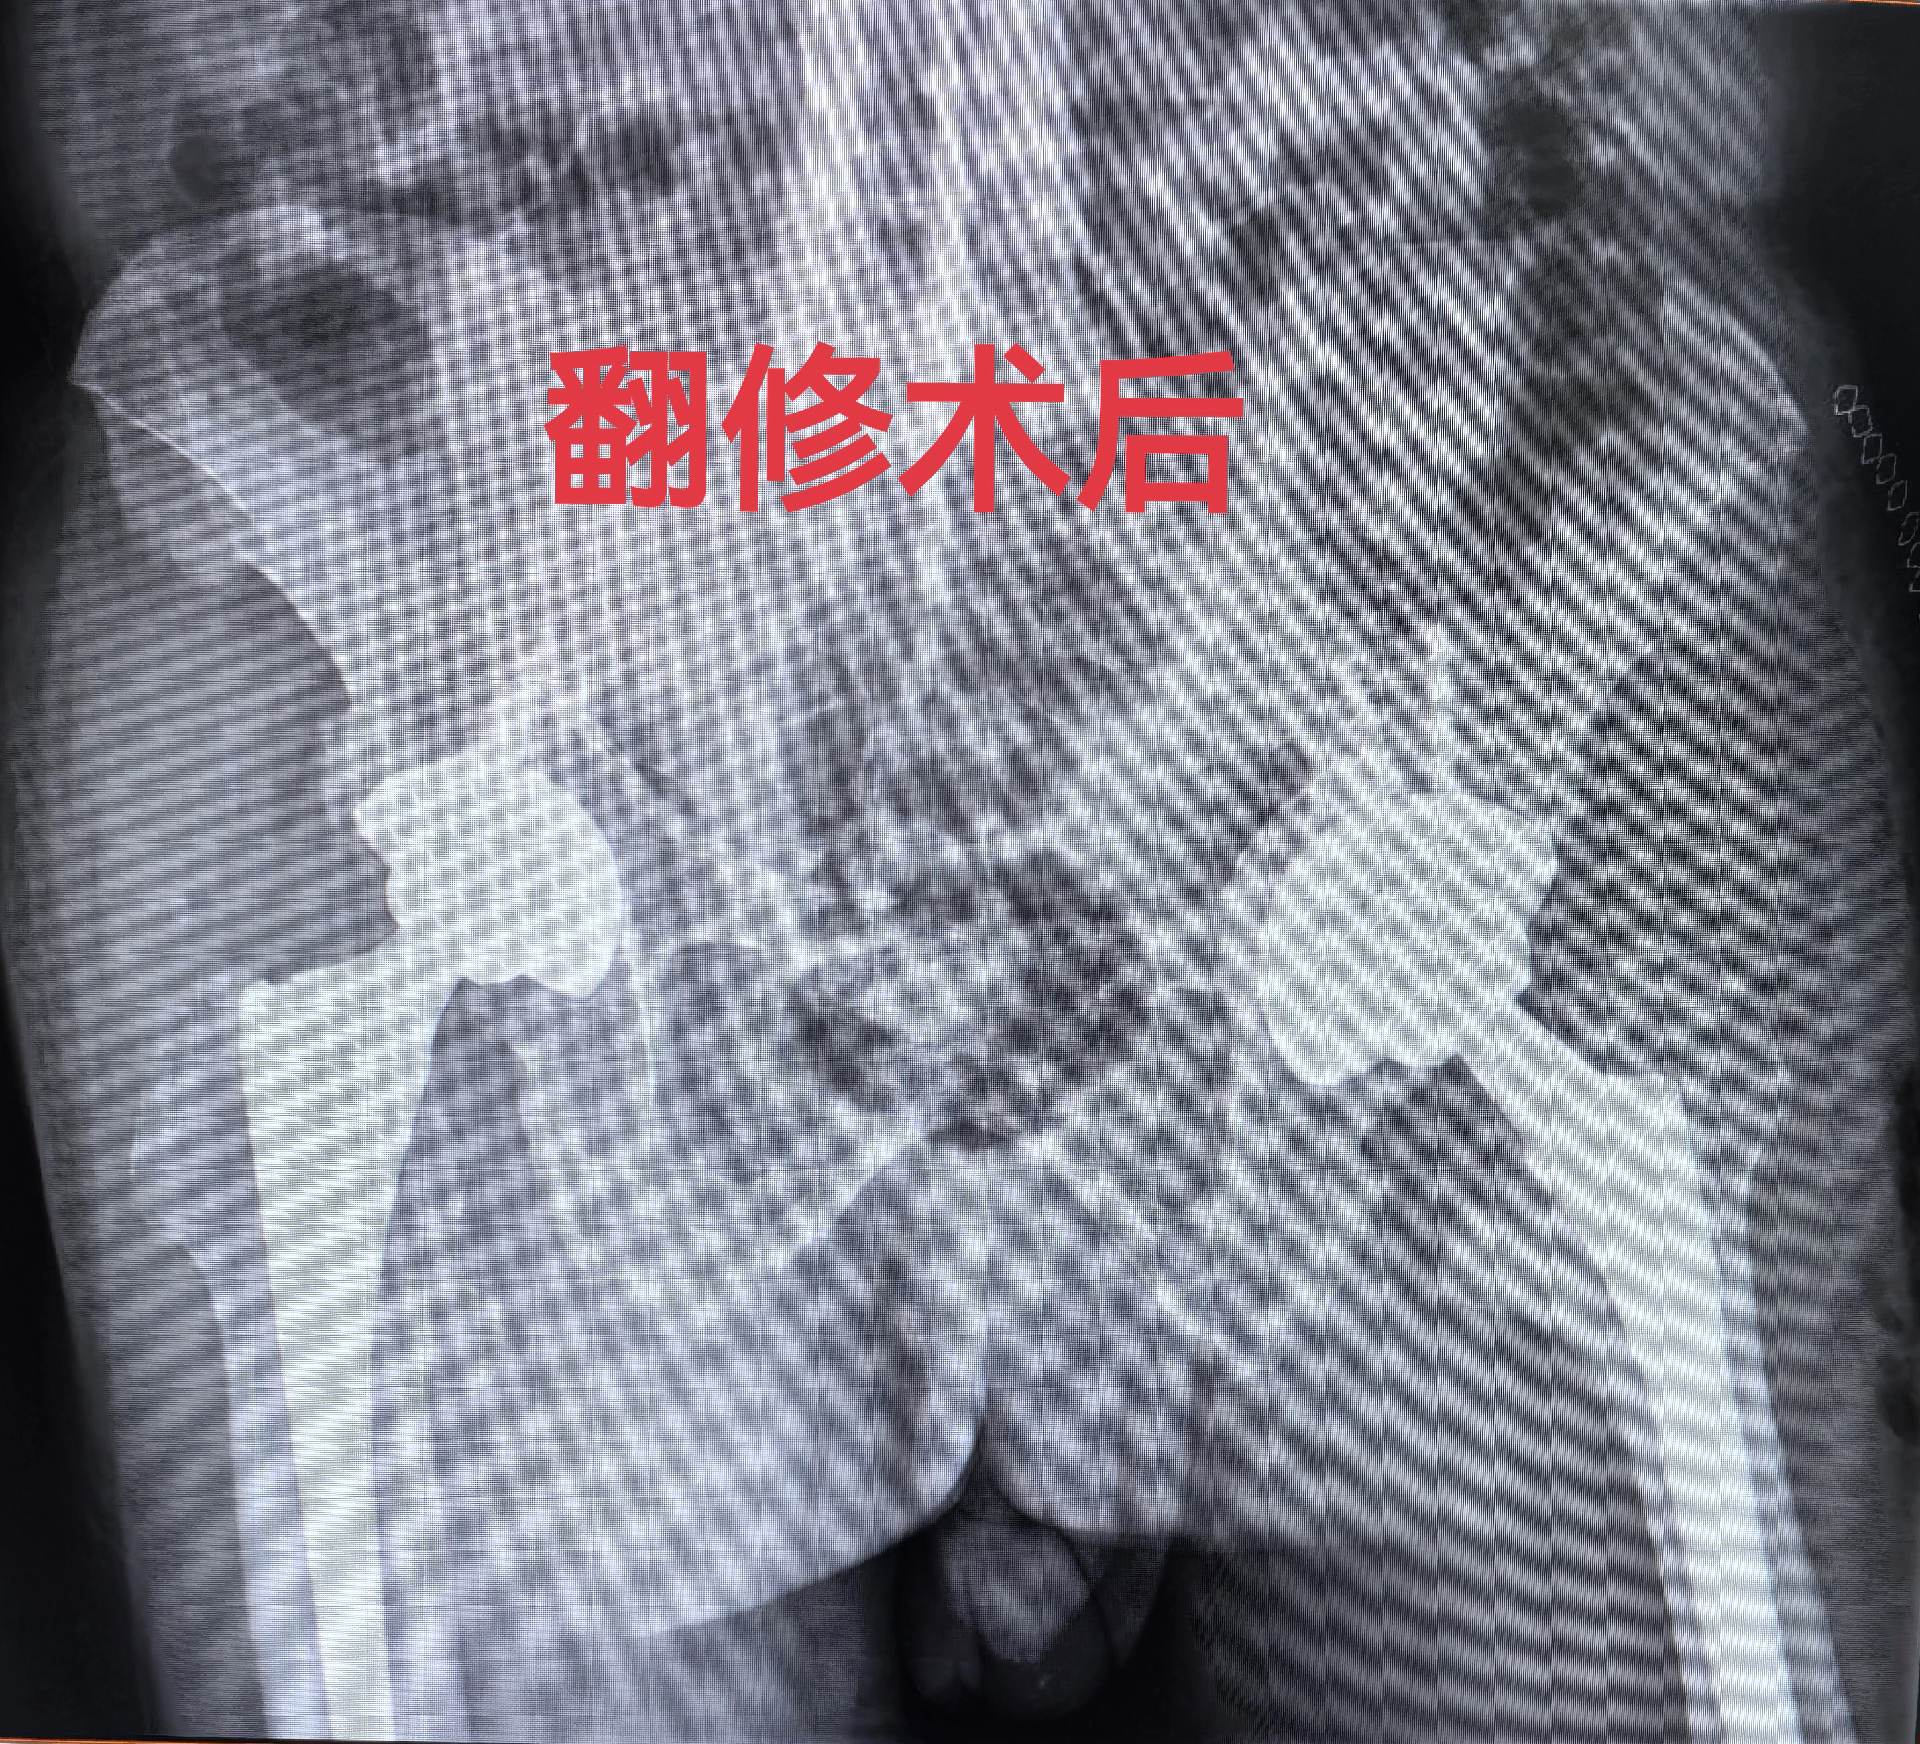

髋关节翻修。强脊炎THA后假体松动,术前短3cm,术后等长。难点:松动的股骨柄远端硬化如何突破?实际操作起来真的不容易。此例虽有插曲,好在医院大平台器械完备,结局满意,术后2天正常下床走路🌹